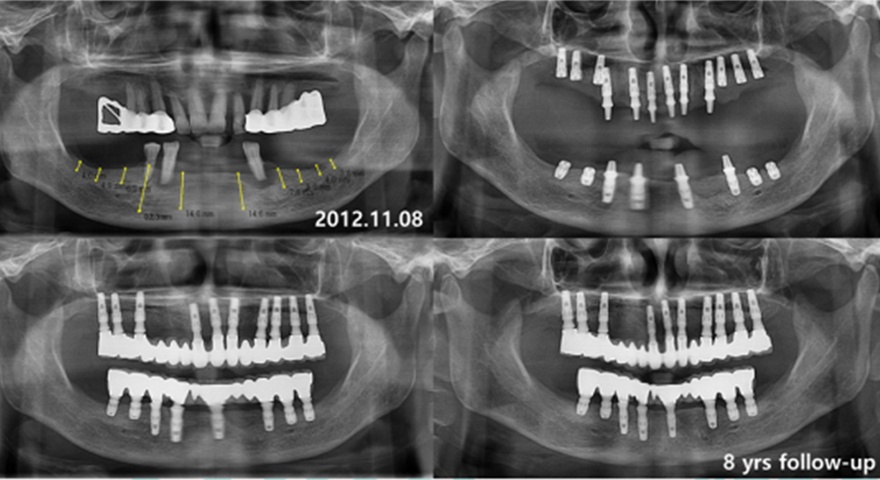

Клінічні випадки:

Одночасне встановлення короткого імплантату INNO

Фото до операції

Передопераційний панорамний знімок

віддалені результати встановлленя короткого імплантату INNO Sub. Short

дані спостережень 8-10 років